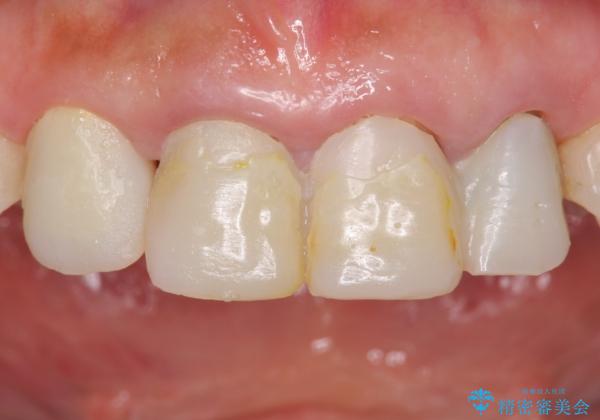

自然な前歯にしたい ジルコニアクラウンでの修復

- 前歯を綺麗にしたいとのことで来院されました。

色調・適合ともに改善するために一度被せ物を外し、歯の形を整えた後に新しい被せ物を装着していきます。